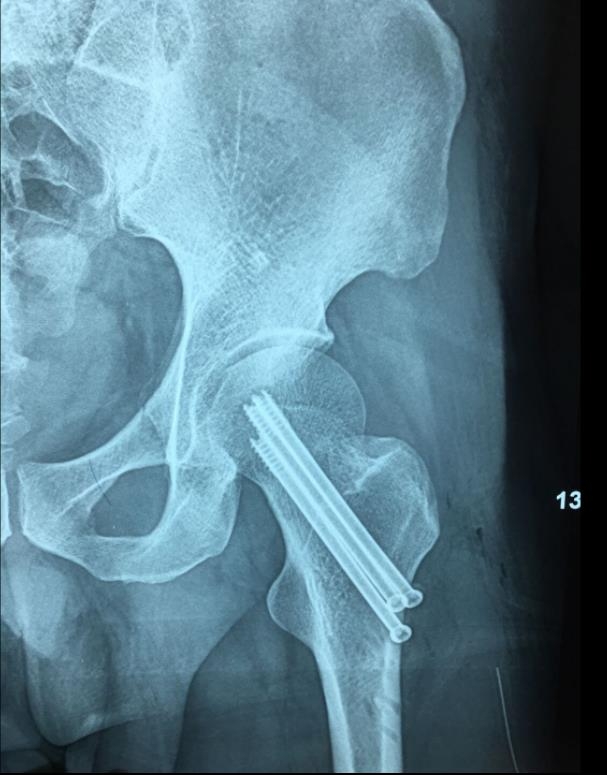

临床病例